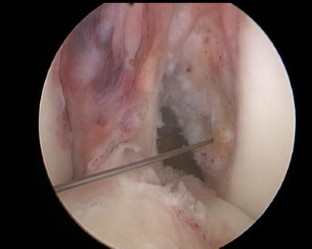

Fig. 2